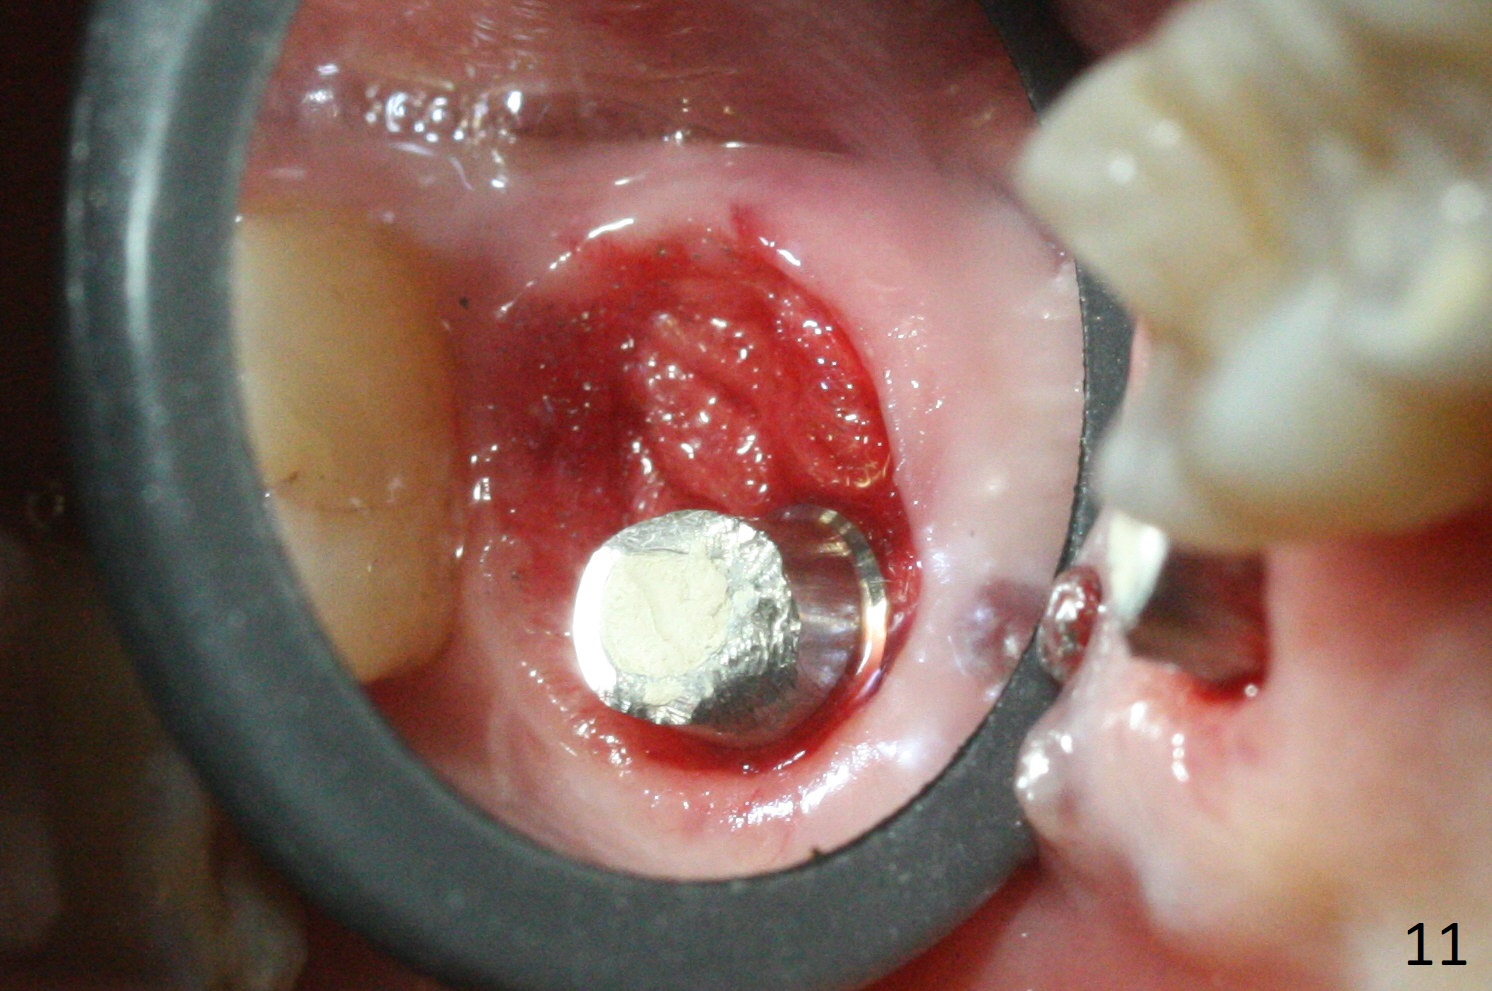

There is a fistula distal to the tooth #2 with deep pocket distopalatally (Fig.1 *), corresponding to palatal root fracture (Fig.2). There is a septum (Fig.3 S) between the buccal (B) and palatal (P) sockets. Osteotomy is initiated in the center of the septum (Fig.4 black circle). In fact the center of the socket is buccal (red circle), in which osteotomy should have been established because of the presence of the distopalatal bony defect associated with the root fracture and the distal fistula. The less ideal initial osteotomy leads to palatal placement of the implant and abutment (Fig.11 vs. 12).